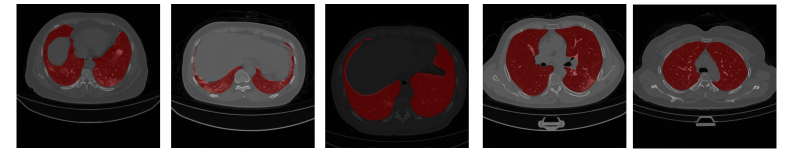

Figure 3 shows visual samples from the datasets used in our experiments: (a) FSS-1000, a natural image dataset illustrated with 10 example classes; and the medical datasets: (b) CHAOS-CT for liver segmentation, (c) Spleen-CT for spleen segmentation, (d) COVID-19 CT for lung infection segmentation, and (e) Cardiac MRI for left atrium segmentation. Segmentation masks are shown in green for FSS-1000 and in red for the medical datasets.

.